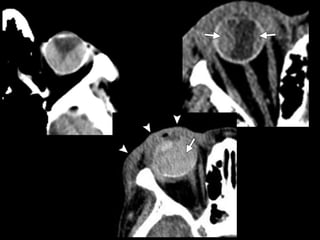

Fracturas simples

• Blowout

• Fx Techo orbitario

• Trapdoor

Trapdoor

Complicaciones

• Orbitarias

• Rotura-atrapamiento RI

• Nervio óptico

• Sme FOS (III,IV,V1,VI)

• Sme ápex (FOS+NO)

• V2 (blowout y Le Fort II)

• Conducto y saco lacrimal (dacriocistitis)

• Tendón canto interno (NOE, telecantus)

Complicaciones • Orbitarias • Rotura-atrapamientoRI • Nervio óptico • Sme FOS (III,IV,V1,VI) • Sme ápex (FOS+NO) • V2 (blowout y Le Fort II) • Conducto y saco lacrimal (dacriocistitis) • Tendón canto interno (NOE, telecantus) • Maxilares • Fx dentales • Infecciones • V3 • Trismus (m. temporal) • Maloclusión